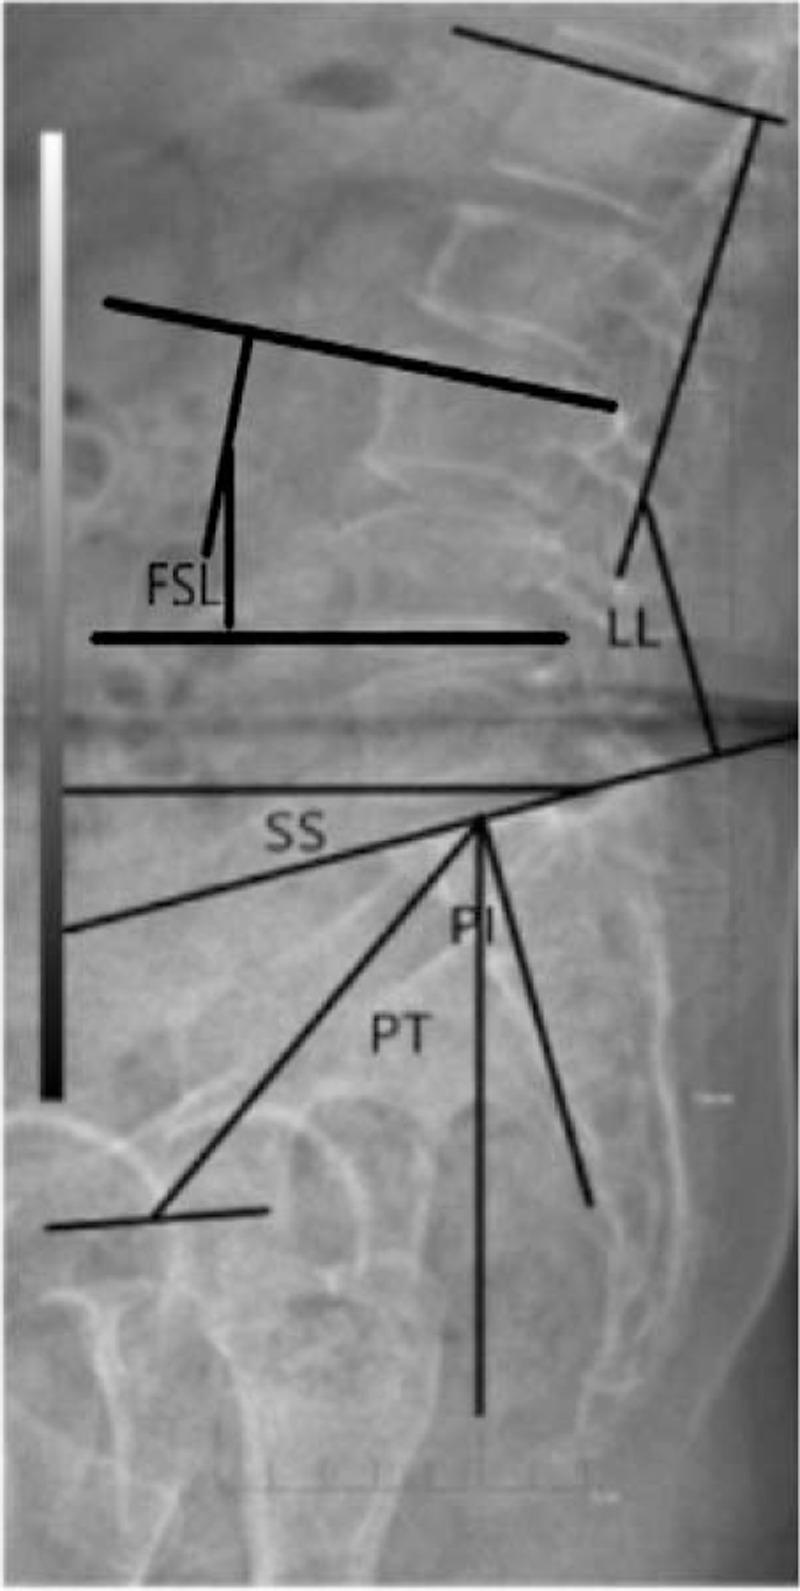

我们回顾性比较了 28 例接受 OLIF(OLIF 组)和 35 例接受 TLIF(TLIF 组)的患者。影像学结果通过椎间盘高度(DH)、椎间孔高度(FH)、融合节段前凸角(FSL)、腰椎前凸角(LL)、骨盆倾斜角(PT)、骨盆入射角(PI)和骶骨倾斜角(SS)进行评估。临床结果采用 Oswestry 功能障碍指数(ODI)和腰痛、腿痛视觉模拟评分(VAS)进行评估。

OLIF 组术后各时间点 DH 和 FH 的改善均高于 TLIF 组(P<.05)。两组间 PT、PI 和 SS 无显著差异(P>.05)。术后两组脊柱骨盆矢状面平衡均得到显著恢复。术后两组腰椎前凸角和融合节段前凸角存在显著差异(P<.05)。两组间症状改善存在显著差异。OLIF 组术后腰痛 VAS 评分和 ODI 低于 TLIF 组(P<.05)。